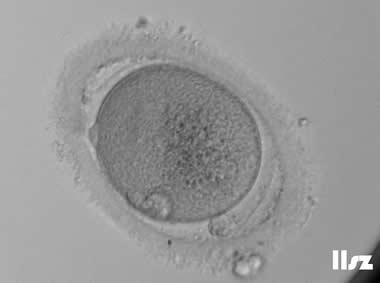

3. 成熟卵母细胞(MII)及其COCs(正常COCs)

卵细胞呈现规则的圆形且颜色较浅,放射冠完全分散,颗粒细胞团较大,排列稀疏。成熟卵母细胞一般在取卵后体外培养2-6小时再行授精。

|  |

| 0小时COCs的MII卵(4x) | 0小时COCs的MII卵(10x) |

|  |

| 2小时COCs的MII卵(10x) | 4小时去颗粒细胞后的MII卵(10x) |